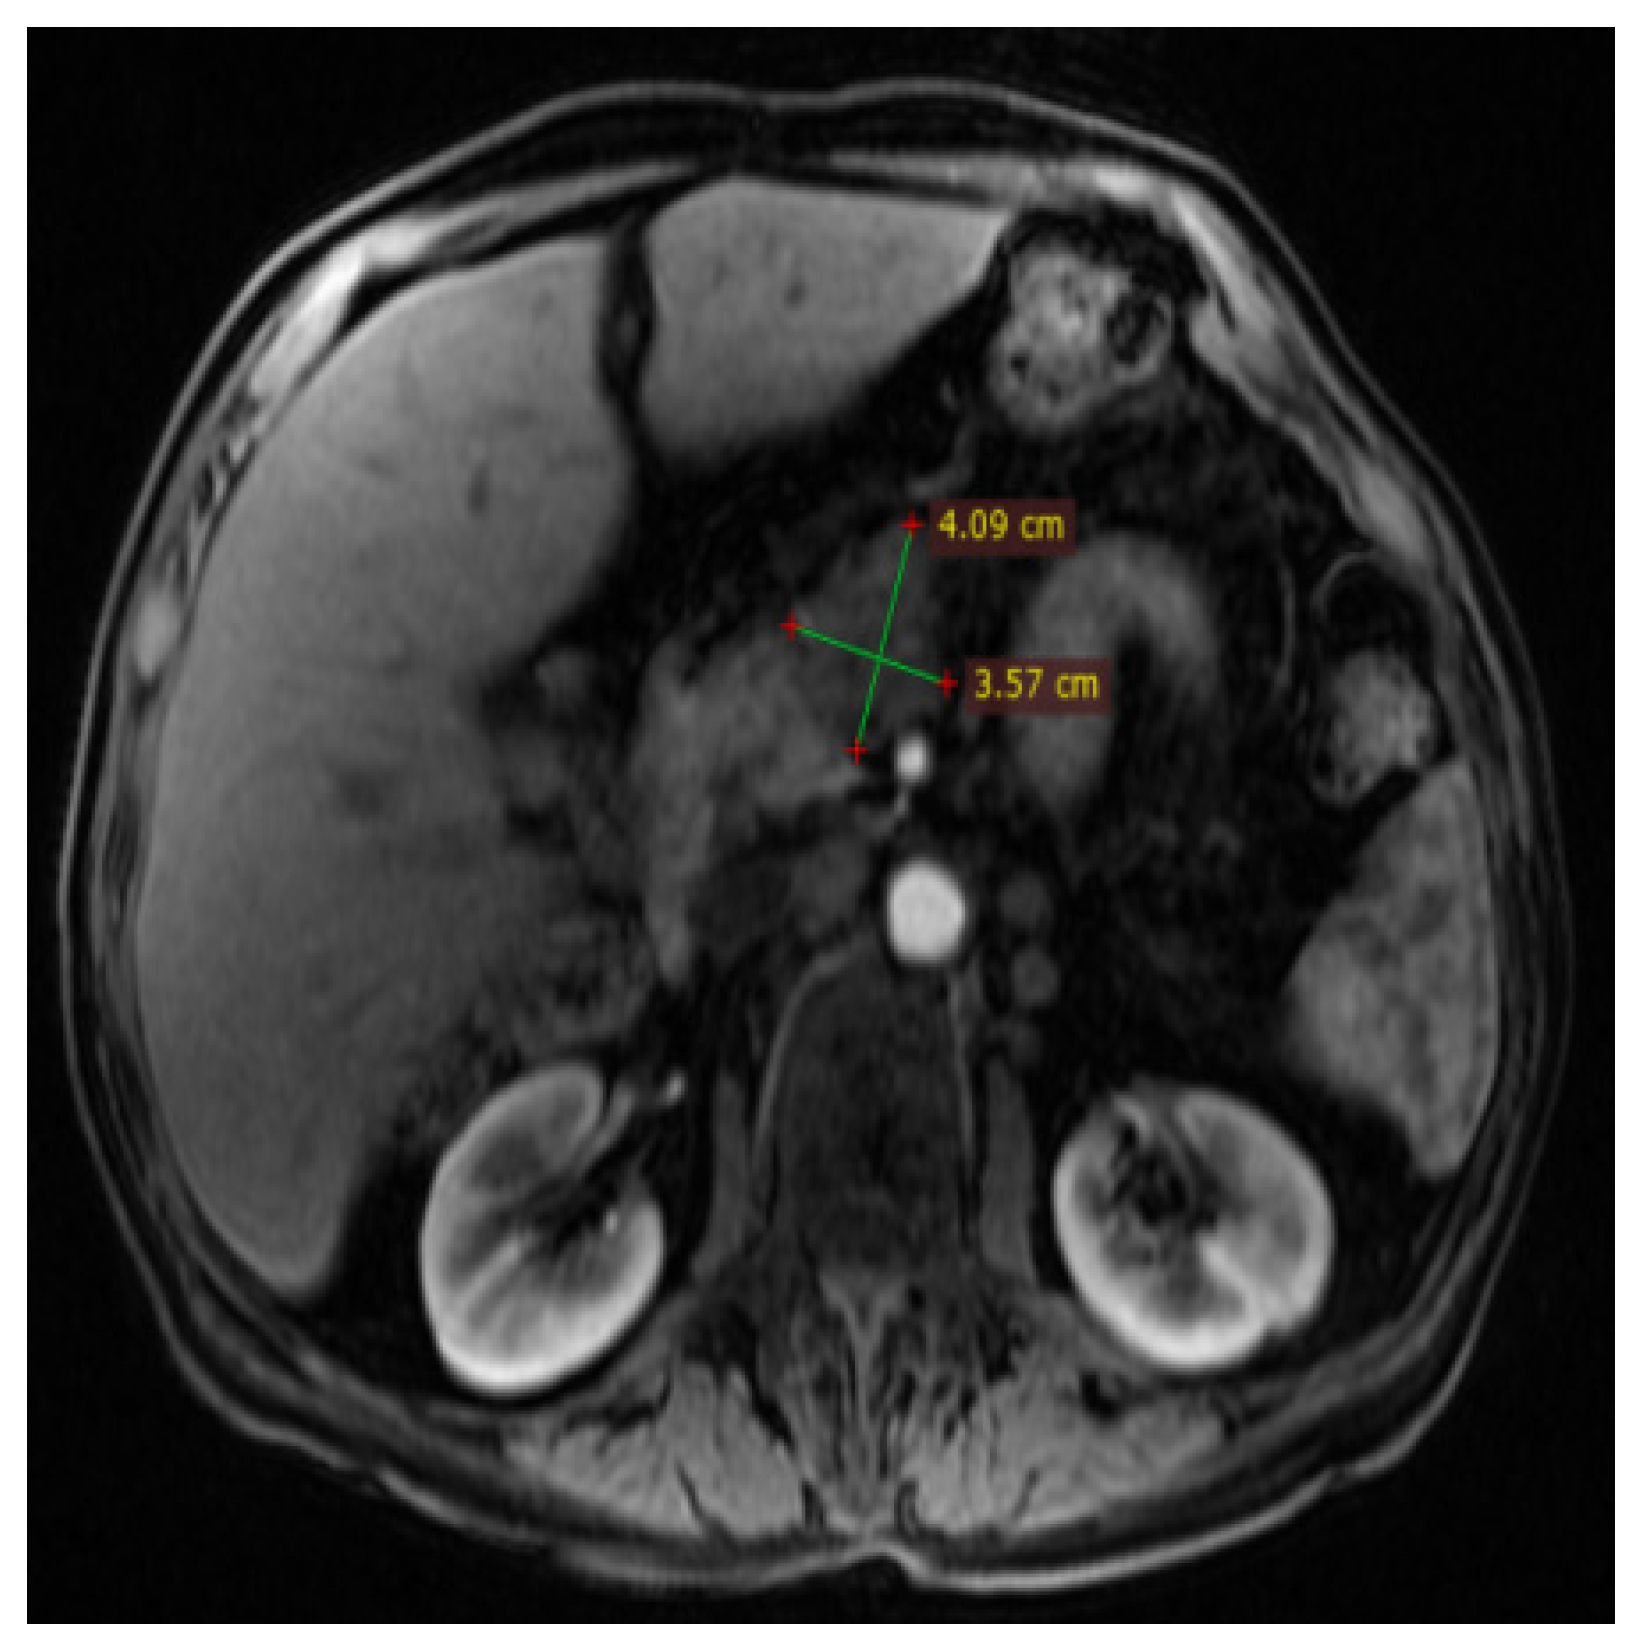

2. Case Report